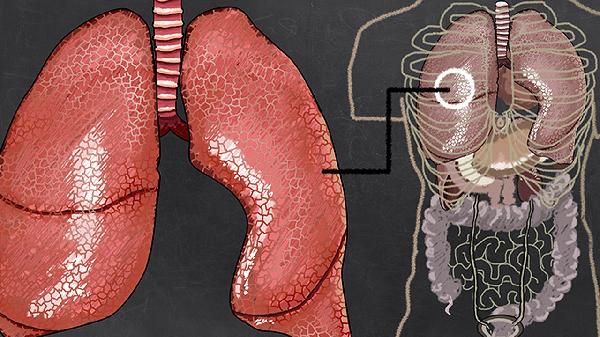

肺气肿患者需保持高蛋白、富含维生素C的饮食以修复肺泡损伤,如鸡蛋、西兰花、柑橘类水果。每日进行30分钟低强度有氧运动如散步、太极可改善肺功能,运动时监测血氧饱和度避免缺氧。居家使用空气净化器减少刺激物吸入,定期做肺功能评估调整治疗方案。突发气促或咳血需立即就医。